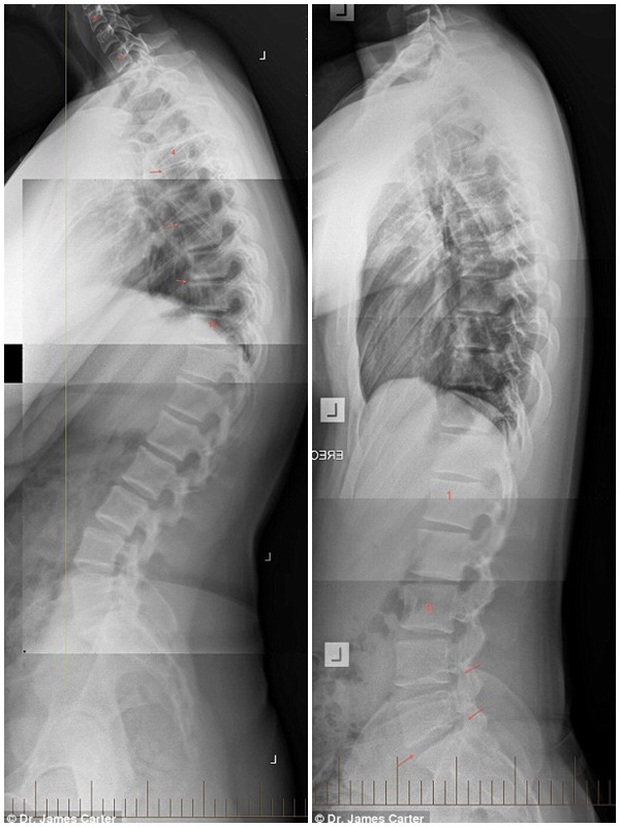

Đây là kết quả

Toàn bộ quy trình sẽ mất khoảng vài giờ. Nhờ vào sự tiến bộ của công nghệ mà bệnh nhân sẽ được về nhà chỉ trong vòng 1 tuần, và có thể quay về cuộc sống bình thường trong vòng 6 tuần hoặc hơn, tùy mức độ nghiêm trọng. Hơn nữa, nếu so với trước kia, độ đau đớn của bệnh nhân cũng giảm đi rất nhiều.